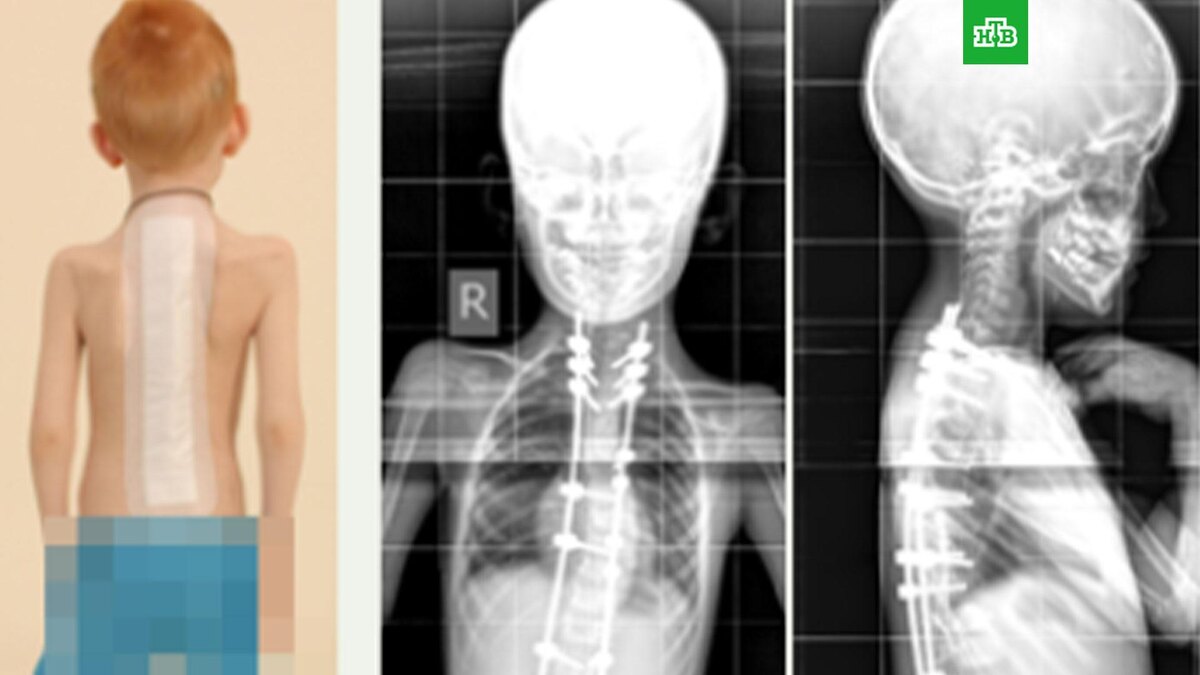

Шесть лет назад ребенок перенес двухэтапную операцию, после чего деформацию позвоночника удалось скорректировать. Сначала врачи сделали гало-тракцию (скелетное вытяжение за кости черепа), а потом установили металлоконструкции для исправления сколиоза.

Из-за школьной травмы у мальчика произошло смещение в шейном отделе, спинной мозг оказался пережат. Ребенка доставили на экстренную операцию в курганский центр имени академика Илизарова.

Полина Очирова, вертебролог, кандидат медицинских наук: «Мы выполнили сложное оперативное вмешательство и исправили аномальное положение шейных позвонков, устранили базиллярную импрессию, стеноз позвоночного канала на уровне краниовертебрального перехода, установили погружную металлоконструкцию, для более прочной фиксации и формирования костного блока мы использовали костный трансплантат».